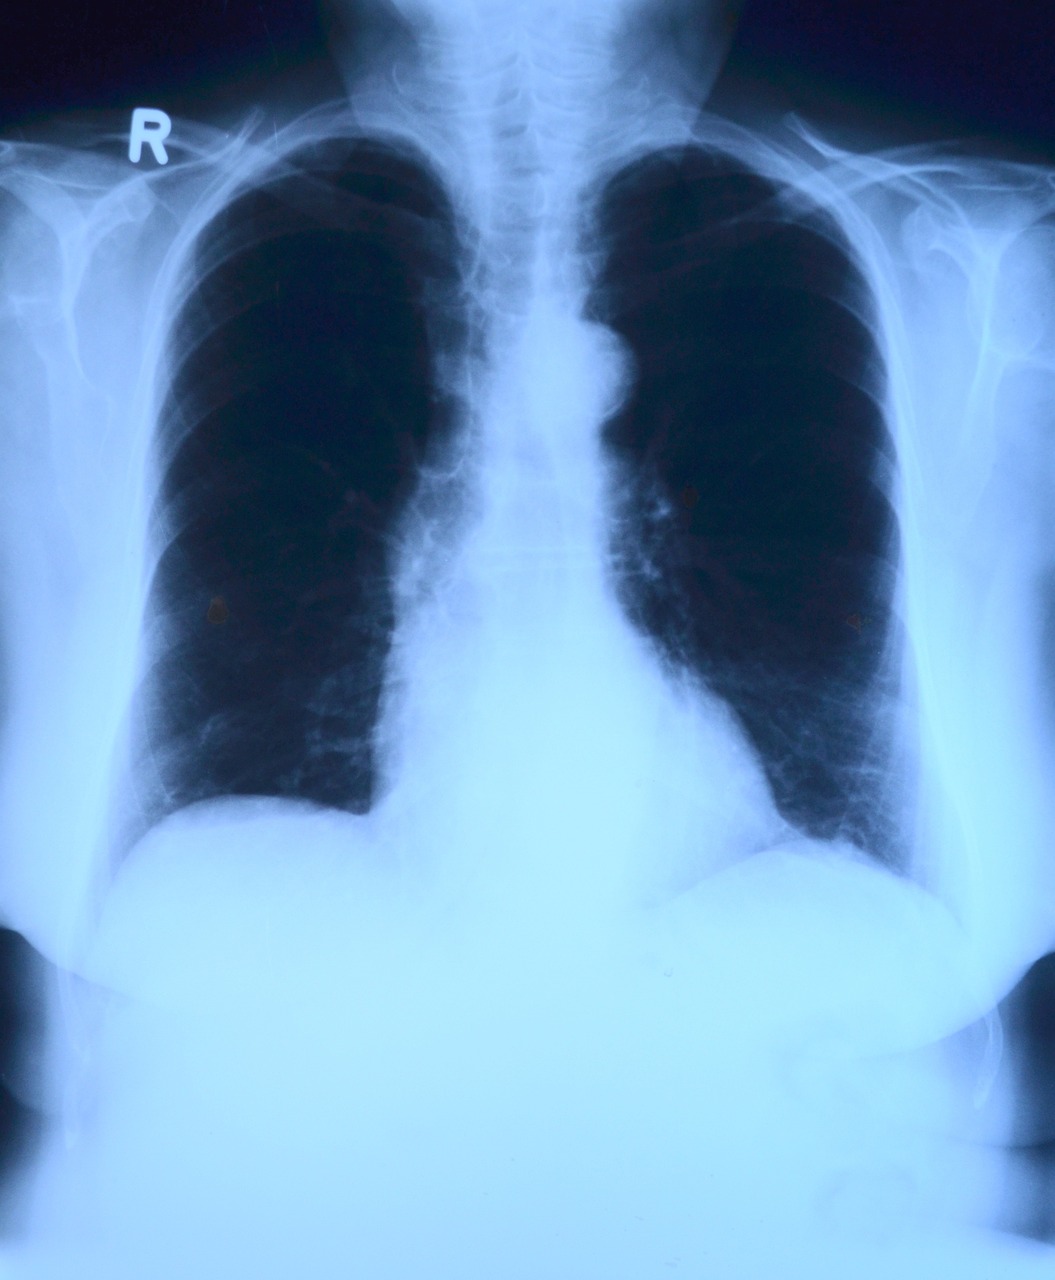

흉부 엑스레이:

비용:1만 원 정도

심장, 폐 및 기타 흉부 구조를 시각화하는 데 도움이 됩니다.